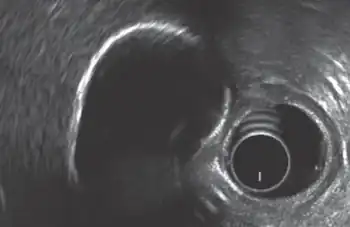

Porcelain gallbladder is a calcification of the gallbladder believed to be brought on by excessive gallstones, although the exact cause is not clear. As with gallstone disease in general, this condition occurs predominantly in overweight female patients of middle age. It is a morphological variant of chronic cholecystitis. Inflammatory scarring of the wall, combined with dystrophic calcification within the wall transforms the gallbladder into a porcelain-like vessel. Removal of the gallbladder (cholecystectomy) is the recommended treatment.